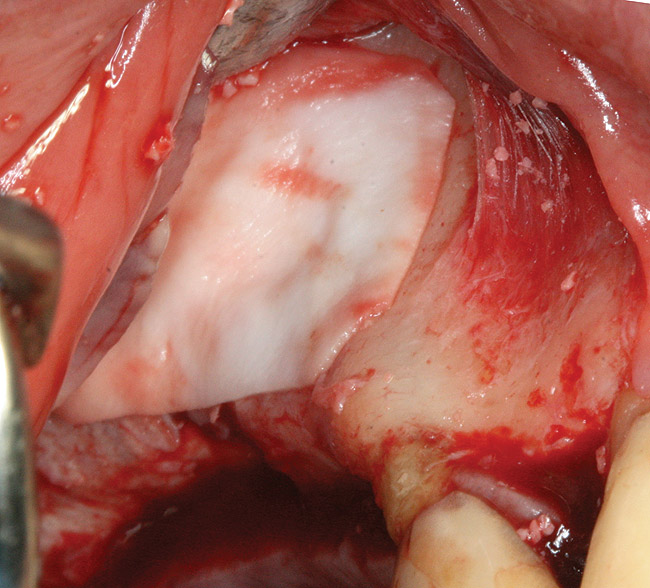

The technique described below is based on a deep buccal full-thickness flap with vertical release in the canine area, followed by creation of a “window” at the lateral wall of the sinus (Figure 2). The bony window is either removed or rotated medially with the sinus membrane and pushed inward. The Schneiderian membrane is then separated from the bone anteriorly, posteriorly, and medially until clinically sufficient space is established (Figure 3). The created space, which occupies the lower third of the sinus, is filled with a bone graft (Figure 4), and the lateral access window is covered with a collagen membrane (Figure 5).

Fig 5. Window is covered with a collagen membrane, and the flap is sutured back into place.

Figure 5